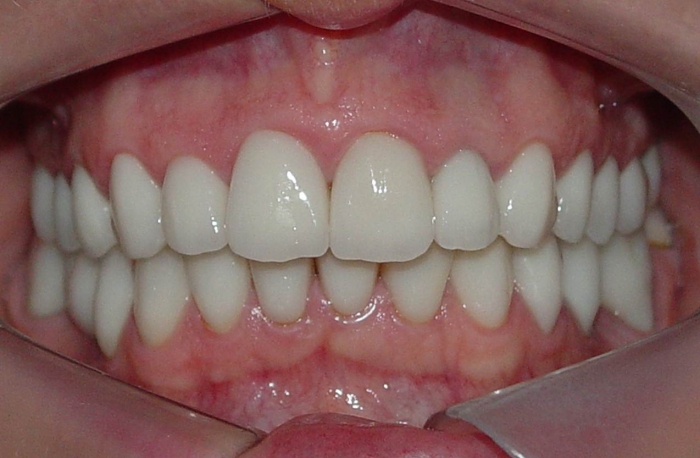

Imagens com facetas e prótese fixa em porcelana sobre implante

Sorriso inicial